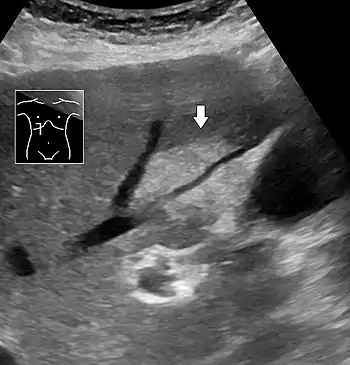

On X-ray computed tomography (CT), the increased fat component will decrease the density of the liver tissue, making the image less bright. Typically the density of the spleen and liver are roughly equivalent. In steatosis, there is a difference between the density and brightness of the two organs, with the liver appearing darker.[12] On ultrasound, fat is more echogenic (capable of reflecting sound waves). The combination of liver steatosis being dark on CT and bright on ultrasound is sometimes known as the flip flop sign.

On abdominal ultrasonography, steatosis is seen as a hyperechoic liver as compared to the normal kidney.

- Abdominal ultrasonography of focal steatosis. It is distinguished from a tumor by not compressing the hepatic vein.